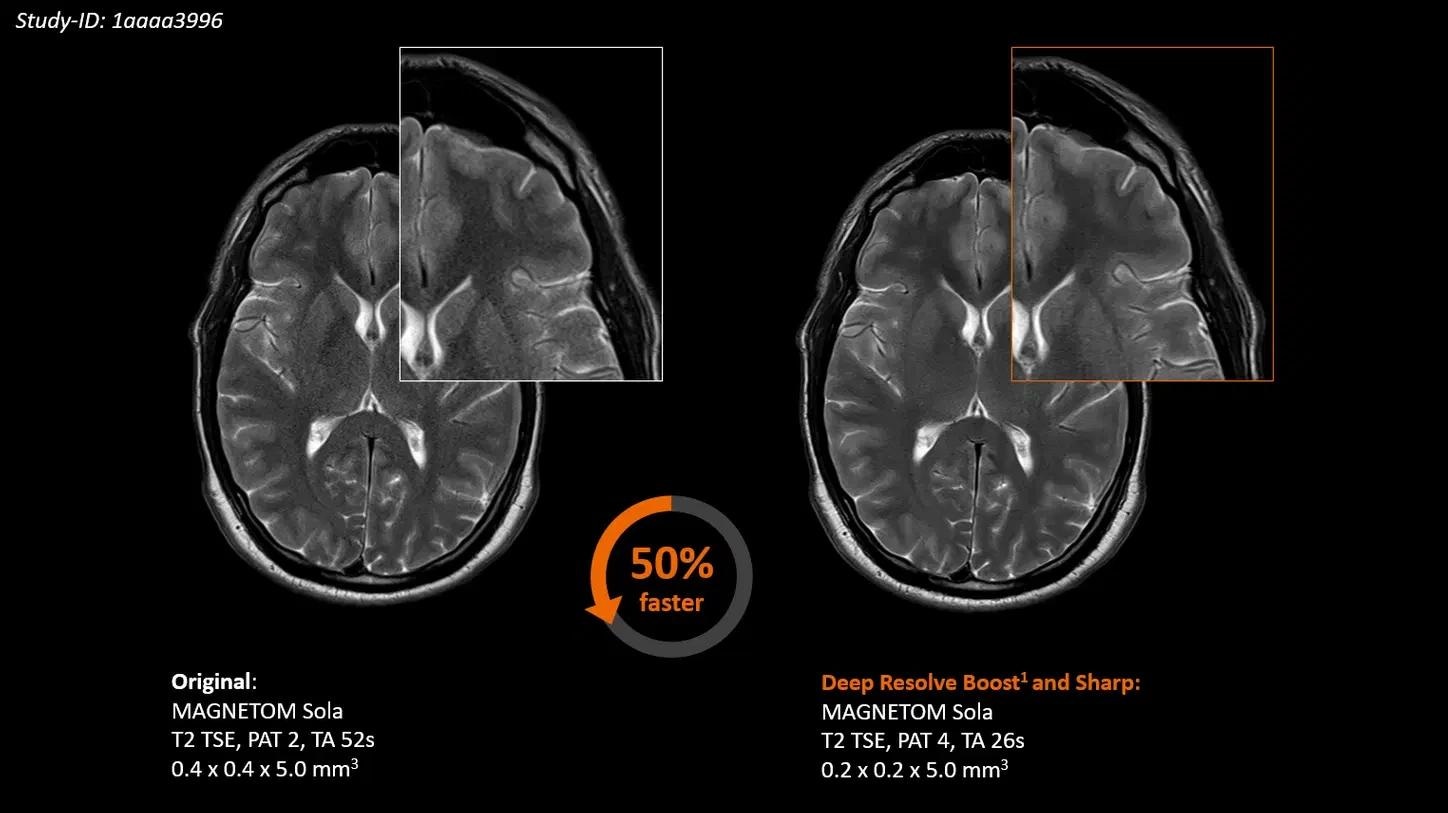

Deep Resolve Boost

Deep Resolve Boost, the first raw data-to-image deep learning reconstruction technology, allows for high SNR and radically accelerated image acquisition.

Deep Resolve

Deep Resolve, an AI-driven image reconstruction technology, speeds up MR scans, thereby making them quicker than ever before.

Clinical routine scans can be up to 50%1 faster thanks to the use of MR acceleration technologies: Compressed Sensing and Simultaneous Multi-Slice.

Deep Resolve, an AI-powered image reconstruction technology, takes advantage of convolutional neural networks to accelerate MR scans. Faster scans boost workflow efficiency while improving the patient experience. Deep Resolve’s raw data-to-image reconstruction and fast acquisition change the MRI game, helping to generate actionable insights that can be diagnostically relevant – faster than ever before.